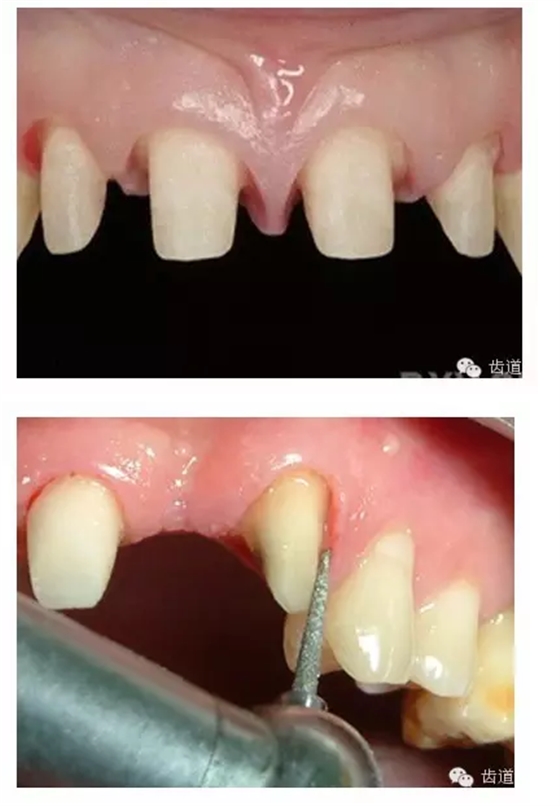

牙體預(yù)備時(shí)應(yīng)考慮的問題

l保護(hù)牙體組織

l基牙具有良好的固位形

l基牙具有良好的抗力形

l預(yù)留修復(fù)體的空間

l邊緣的適合性

l保護(hù)牙周組織

l多個(gè)基牙時(shí)就位道的調(diào)節(jié)

l實(shí)際備牙產(chǎn)生的問題

2. 基牙具有良好的固位形

摩擦力

正壓力:即修復(fù)體的密貼程度(小于0.2mm)

表面粗糙程度

牙的外形及洞形的幾何形狀:主要是牙體制備出一定聚合角度產(chǎn)生的阻擋作用